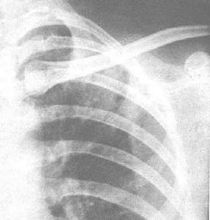

病變情況及類型32例患者均為繼發性肺結核,有5例同時合併結核性胸膜炎,或包裹性胸腔積液,病變限於一個肺野者3例,2個肺野10例,3個肺野11例,4個肺野7例,5個肺野1例。

影像學變化32例完成治療後X線胸片或肺CT片,3例滲出性病變完全吸收,24例以滲出伴乾酪性病變者有18例明顯吸收,5例伴有胸腔積液者3例積液完全吸收,2例形成包裹積液伴胸膜肥厚。